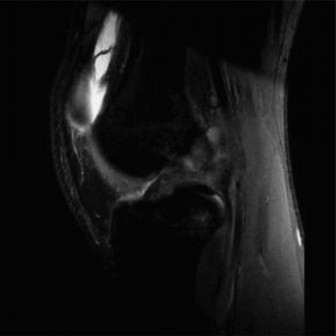

A 30-year-old construction worker presents with chronic low back pain and radicular symptoms to his right leg. He has undergone 3 months of physical therapy, NSAIDs, and activity modification without significant relief. MRI shows a contained L4-L5 disc protrusion without significant migration, impinging the L5 nerve root. Neurological exam reveals mild weakness in right great toe extension (4/5) but no bladder/bowel dysfunction. What is the most appropriate next step?

Explanation:

Given the failure of 3 months of conservative management for persistent radicular pain due to a disc protrusion and mild, non-progressive motor weakness, a transforaminal epidural steroid injection is a reasonable next step. It can provide significant pain relief by delivering anti-inflammatory medication directly to the affected nerve root. Surgical intervention (microdiscectomy) is typically considered for intractable pain after a trial of epidural injections, or for progressive neurological deficits. Lumbar fusion is overly aggressive for this presentation. Continuing conservative management for *another* 3 months without any specific escalation may be prolonged, and psychological counseling is not the primary intervention for this specific clinical picture, although it can be part of a multidisciplinary approach for chronic pain.